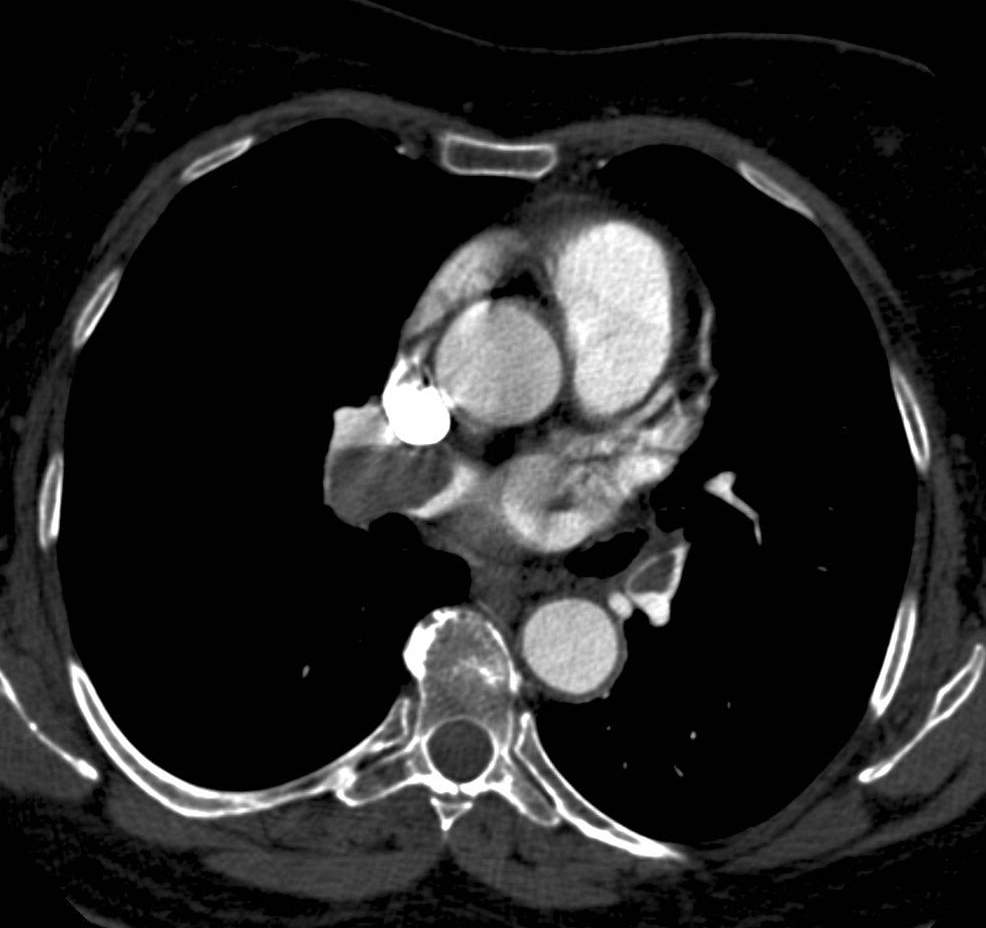

8.1.8. Cardiac tumors

The most common primary cardiac tumor is the myxoma which can originate from the endocardium or the valves. They typically appear as mobile, intra-cavital masses (on echocardiography, CT or MRI). The most common tumor originating from the myocardium is rhabdomyoma, often appearing multifocally. Secondary tumors of the heart can be metastases from true hematogenous spreading; the primary tumors in these cases are most often breast-, lung carcinomas or melanoma but tumors can also spread directly from nearby thoracic tissues, through direct propagation, most commonly from pulmonary tumors. Echocardiography can suspect tumorous infiltration of the cardiac wall or chamber; however, it is unable to show integrally the possible extra-cardiac tumor component and cannot differentiate securely tumorous lesions from the normal myocardium. Another fundamental question that need to be answered is how much of the actual intra-cavital pathologic lesion is made up of viable tumor tissue and how much of it is a thrombotic growth on its surface. This is best assessable with MRI examination. Tumors with extra-cardiac, mediastinal or pulmonary infiltration might require the use of CT examination in order to determine the full extent of the tumor components.